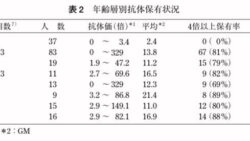

トレンド 天然痘ワクチン